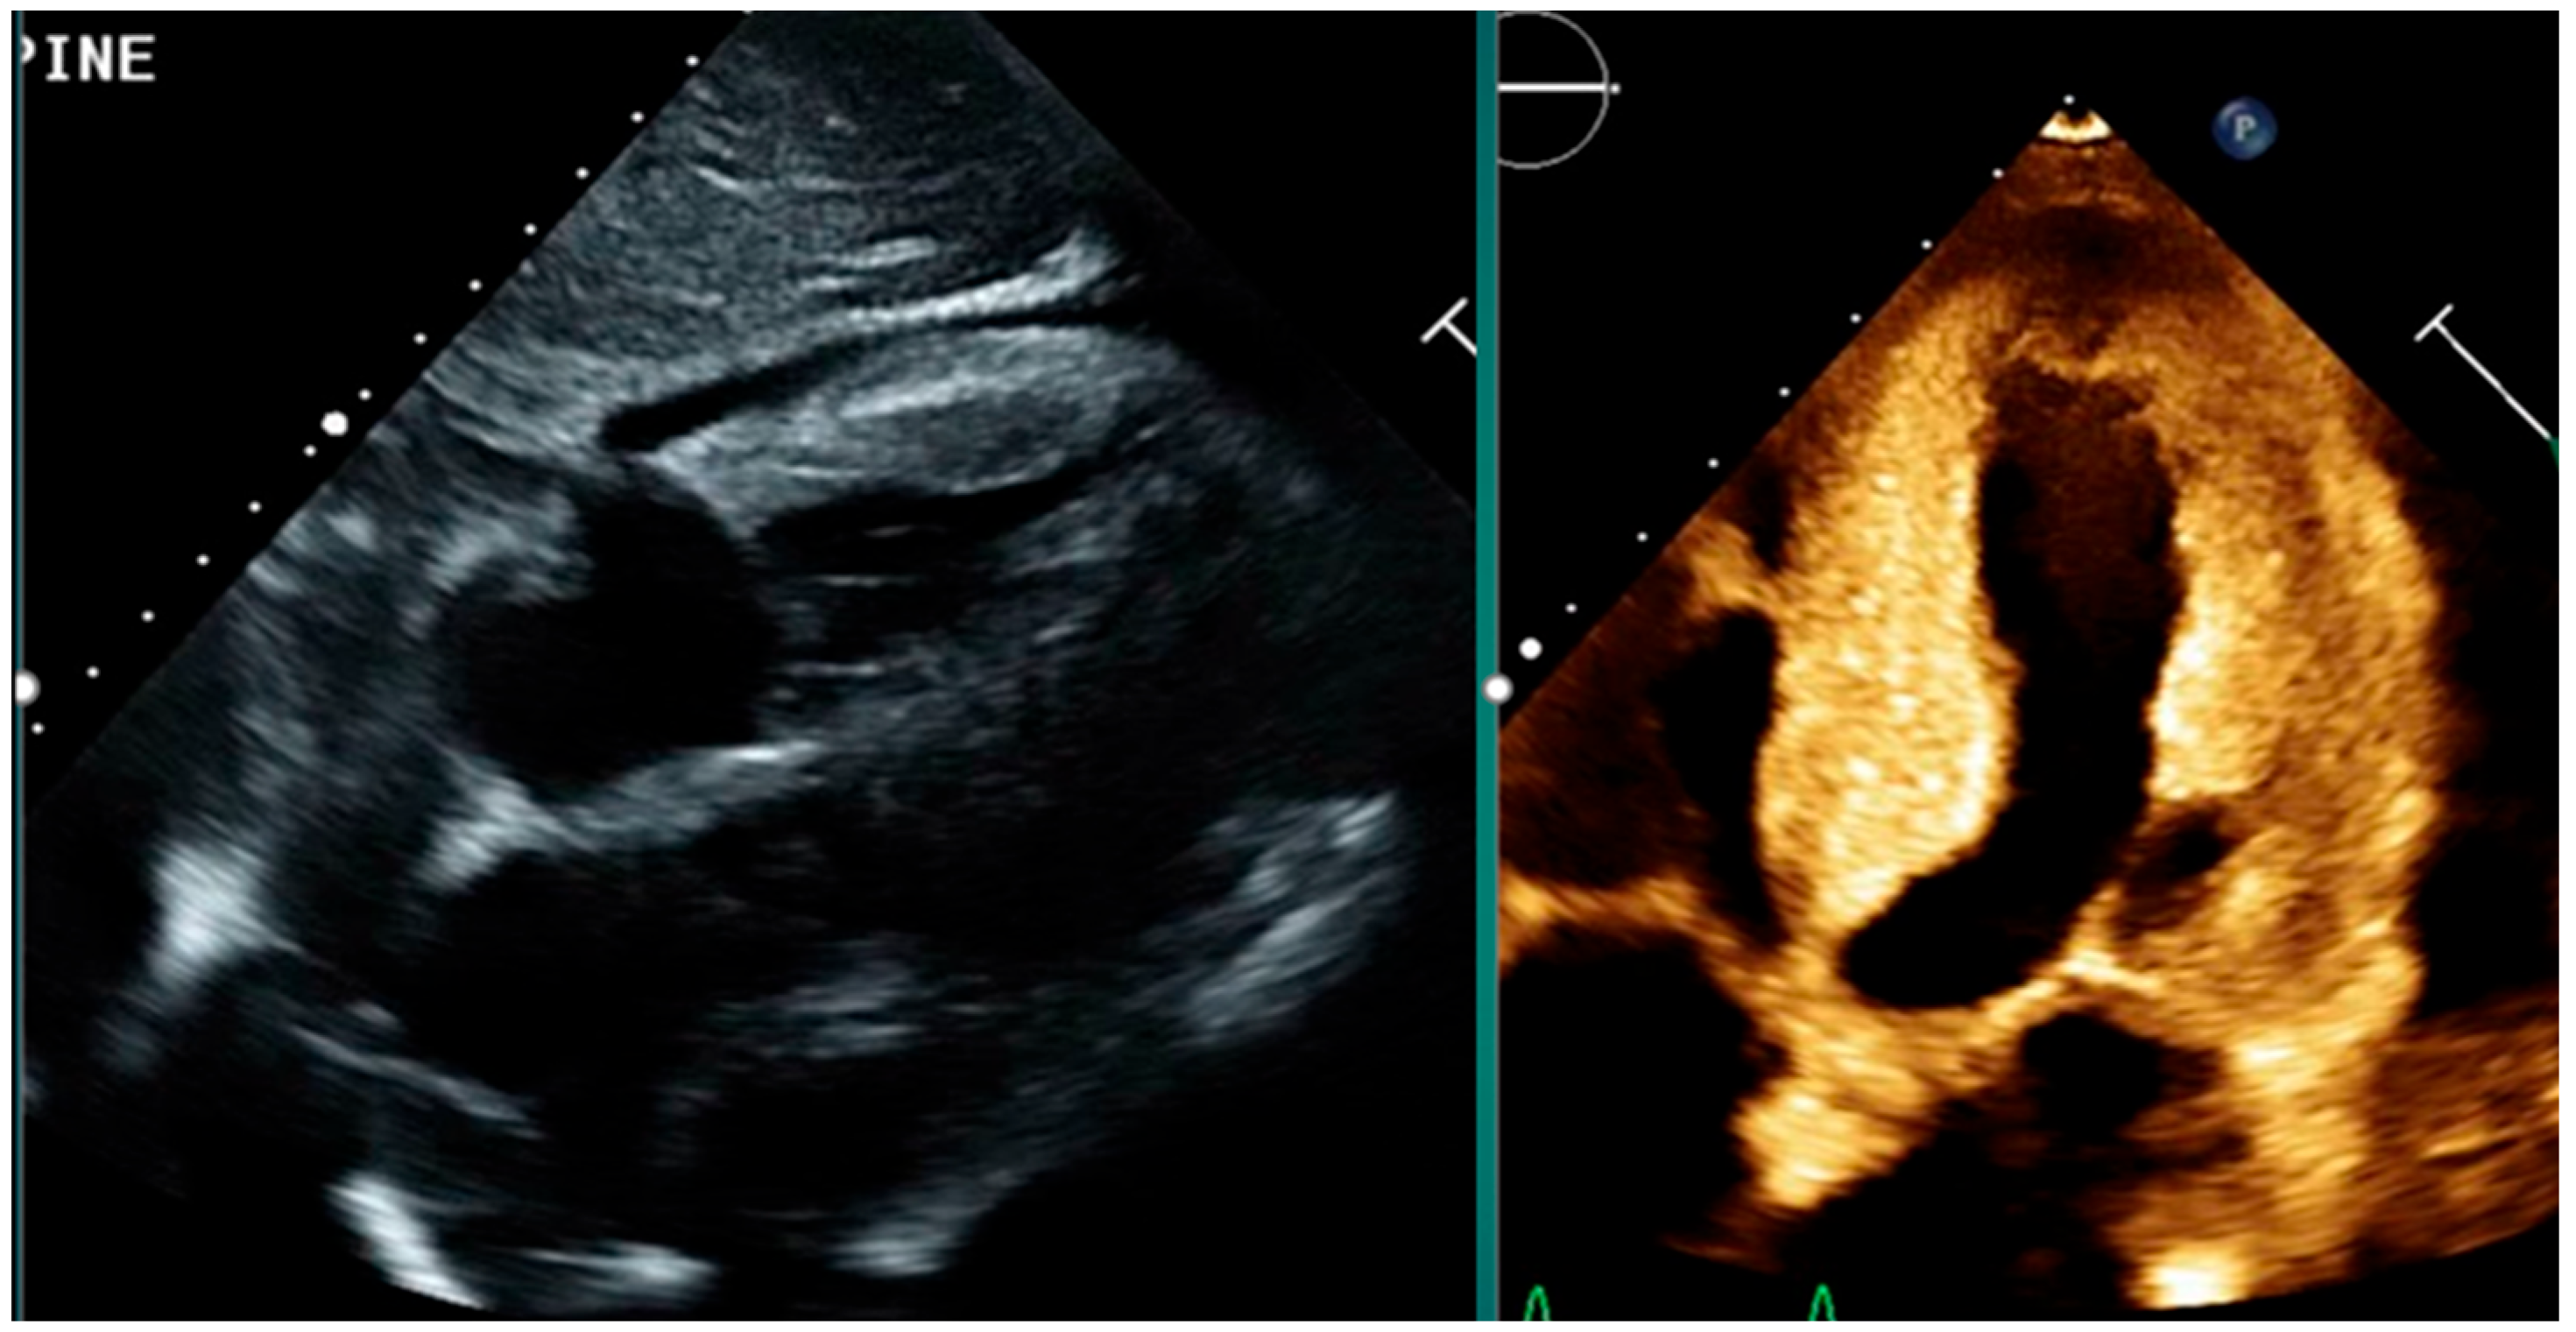

4. Echocardiography in Cardiac Amyloidosis

- Increased left ventricular (LV) wall thickness, often concentric and symmetric.

- Sparkling or granular myocardial texture due to amyloid infiltration.

- Biatrial enlargement and dysfunction.

- Thickened valves and interatrial septum.

| Echocardiography | - Increased LV wall thickness- Granular myocardial texture- Pericardial effusion- Apical sparing on strain- LA dysfunction on tissue Doppler | - First-line imaging- Widely available- Assesses structure and function- Suggests amyloid pattern | - Non-specific findings- Limited tissue characterization |

| Strain Imaging (GLS) | - Relative apical sparing (“cherry-on-top”)- Longitudinal strain analysis | - High sensitivity/specificity for amyloidosis- Early myocardial dysfunction assessment | - Strain abnormalities may overlap with other cardiomyopathies |